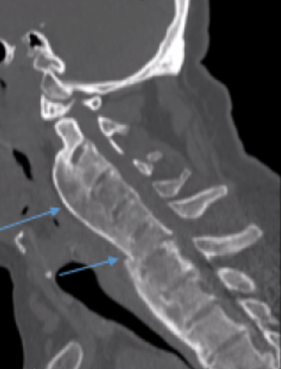

1) Ossification of the posterior longitudinal ligament (OPLL)

OPLL is present in approximately 50% of patients with cervical DISH and is most common in the cervical spine, representing 75% of all OPLL cases (2). OPLL may occur in the thoracic and lumbar spine as well. It is twice as common in men than women and slightly more common in Asian countries (3). Patients with OPLL may be asymptomatic or present with symptoms consistent with central canal stenosism such as radiculopathy and myelopathy. Cord injury from minor trauma is also a greater risk in those patients with OPLL, particularly in the cervical spine. CT imaging is the best imaging modality to assess the degree of central canal stenosis. Treatment may be conservative, but surgical treatment may be appropriate when neurologic symptoms are present. Great care and caution should be taken when assessing and treating your patients with OPLL.

2) Chalk stick fracture

The most important risk fracture of DISH with or without OPLL is the risk of a chalk stick fracture due to ankylosis of the spine. Most all practitioners easily remember the risk of chalk stick (aka carrot stick) fracture in inflammatory spondyloarthropathies such as ankylosing spondylitis, but often fail to recognize DISH as a risk factor for this same type of fracture. A chalk stick fracture is an unstable fracture through ankylosed vertebrae, regardless of the etiology of the ankylosis. These fractures can occur following minor trauma, such a trip on a curb, in conditions such as AS and DISH.